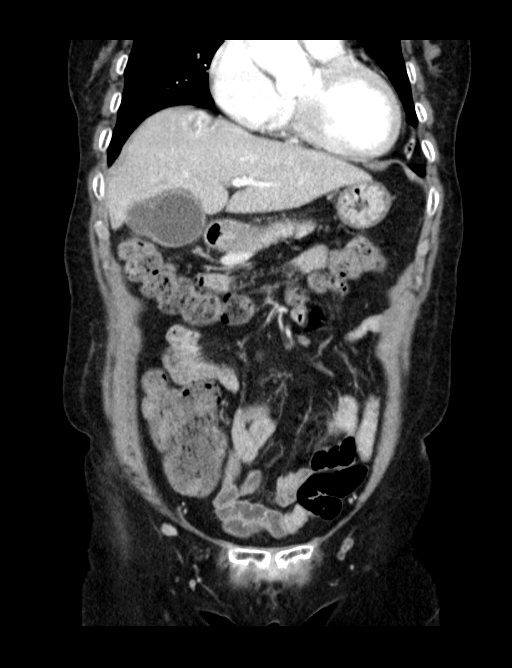

그 다음날 내과에서 CT를 의뢰해서 촬영한 영상입니다. 간의 지붕부위에 혈관종이 떡하니 자리를 잡고 있더군요. 물론, 이렇게 혈관종인 경우야 환자에게 별다른 의미는 없겠습니다만, 초음파검사를 진행할 때 술자가 얼마나 주의깊게 이런 난해한 부위를 확인하려고 하느냐 아니냐에 따라 혈관종이나 단순낭종이 아닌 초기 간암같은 치명적인 병변을 놓치게 될수도 있을겁니다. 환자가 통증때문에 제대로 검사에 협조하기 어려웠던 점을 감안해 검사를 완전히 끝내지 못했다는 언급만 했더라도 검사하는 의사로서는 최선을 다했다고 말할 수 있었지만, 그걸 못한 점은 저도 변명하기 어려운 오점이라고 생각합니다.